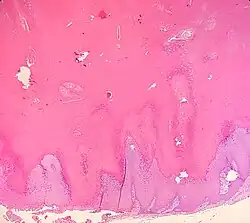

Upper back of a middle-aged man. Present for years.

Verrucous cysts are a cutaneous condition that resemble epidermoid cysts except that the lining demonstrates papillomatosis.[1]: 681